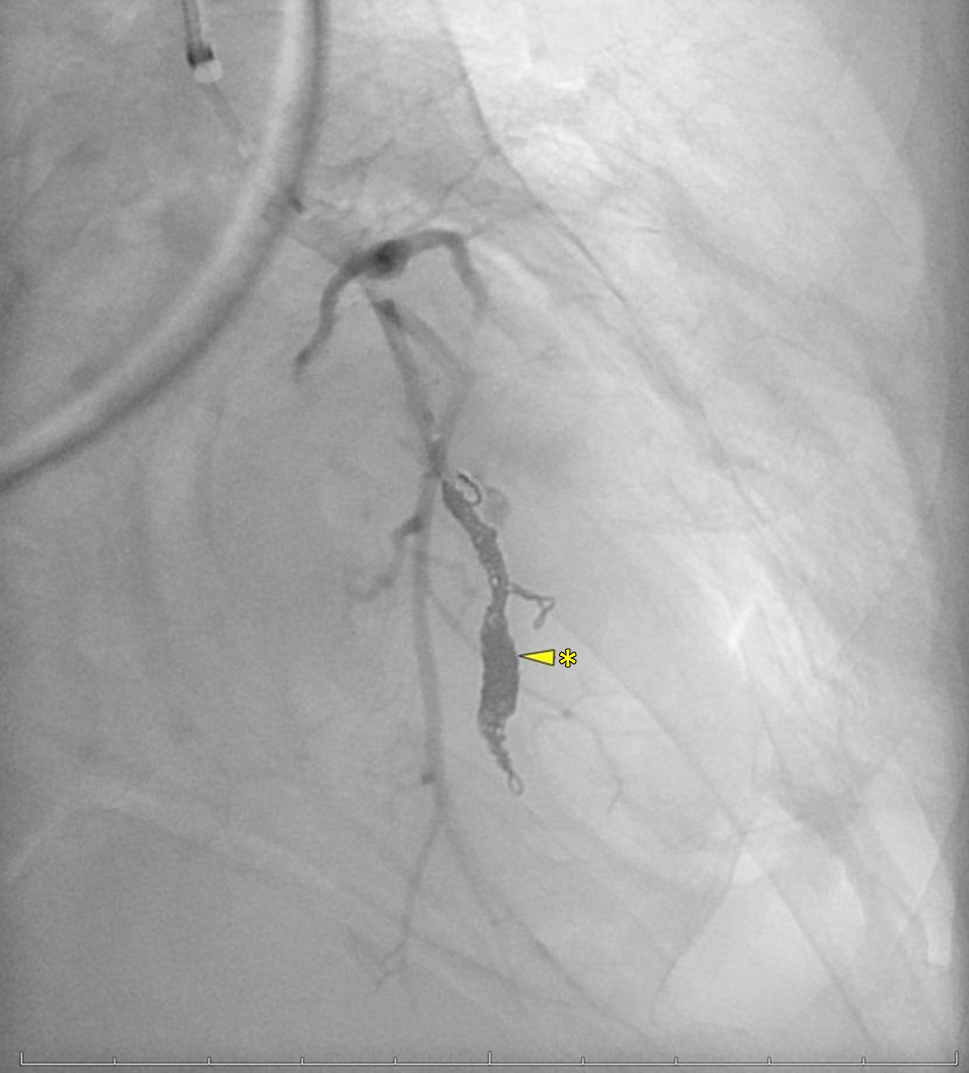

Fig. 5

The segmental artery is embolized with coils (arrow with asterisk)